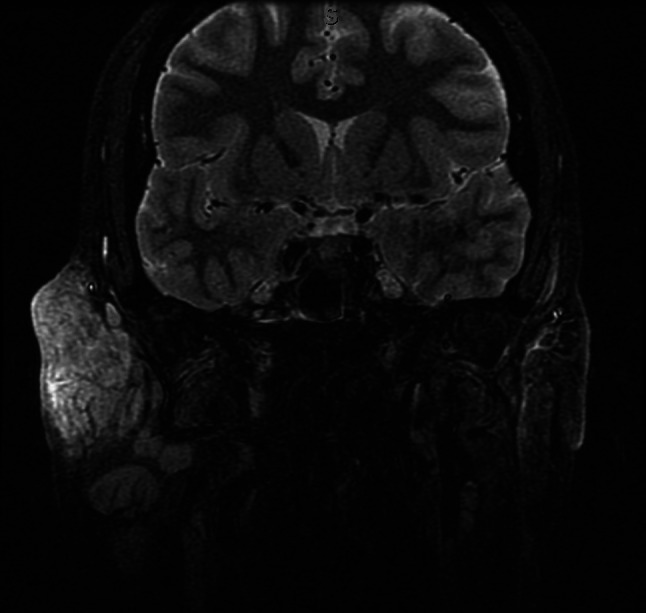

A 39 year-old male presented to the University of Texas Medical Branch Otolaryngology clinic with facial pain and cosmetic deformity caused by a slowly growing right facial mass. The mass first appeared in 2015, but the patient did not seek care until 2017. At that time, a community plastic surgeon performed a surgical resection. The lesion recurred shortly thereafter and the patient was then treated with systemic corticosteroids without improvement. Upon presentation to our clinic, physical exam revealed a large right facial mass extending from the supraorbital rim superiorly to below the angle of the mandible inferiorly without overlying skin change. CT and MRI demonstrated a subcutaneous heterogeneously enhancing mass involving the right parotid as well as infra-temporal and supraorbital soft tissues without extension into the orbit (Figs. 1 and 2). Additionally, multiple pathologic lymph nodes were seen in the region surrounding the right parotid as well as right levels II-IV.

Fig. 2.

Short TI Inversion Recovery sequence (fat suppression) showing enhancement of right sided preauricular lymphadenopathy